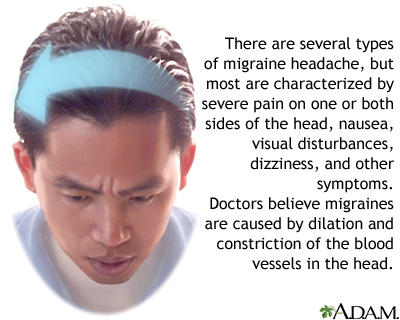

A migraine is a type of headache. It may occur with symptoms such as nausea, vomiting, or sensitivity to light and sound. In most people, a throbbing pain is felt only on one side of the head.

A migraine headache is caused by abnormal brain activity. This activity can be triggered by many things. But the exact chain of events remains unclear. Most medical experts believe the attack begins in the brain and involves nerve pathways and chemicals. The changes affect blood flow in the brain and surrounding tissues.

There are two main types of migraines:

Migraine cause - illustration

Migraine cause

illustration

Migraine cause - illustration

Migraine cause

illustration